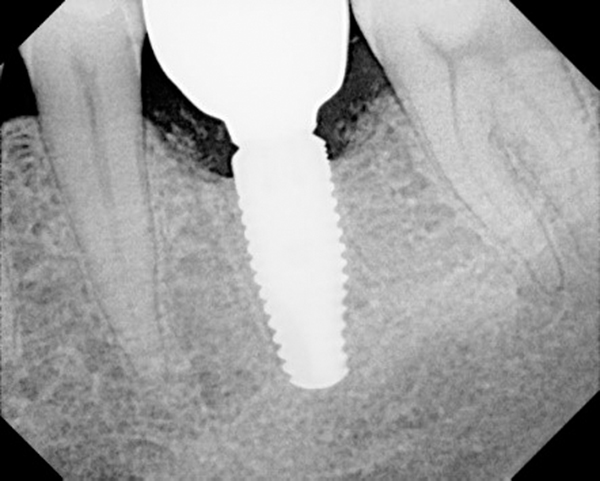

See more ideas about crystals, rocks and minerals, stones and crystals. The concept refers to placing screwed or friction fit restorative abutments of narrower diameter on implants of wider diameter, rather than placing abutments of similar diameters. In dentistry, platform switching is a method used to preserve alveolar bone levels around dental implants.

Alveolar bone is that part of the maxilla and mandible which supports the teeth by forming the other attachment for fibres of the periodontal ligament (fig. In dentistry, platform switching is a method used to preserve alveolar bone levels around dental implants. Crestal bone loss has been documented as one of the important factors that affect the long term prognosis of implant supported restoration 16. The concept refers to placing screwed or friction fit restorative abutments of narrower diameter on implants of wider diameter, rather than placing abutments of similar diameters.